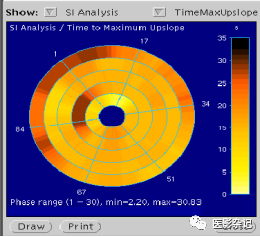

在MRI心脏功能学和灌注检查影像分析中,都会用到心脏分区和牛眼图功能。同时,会大量使用电影播放(Cine)功能。

*左心室短轴位冠脉心肌供血分区示图: 供血分区:0-3、13-15 左前降支供血区,4-7 左回 旋支供血区,8-12 右冠供血区。心肌壁划分:前壁0-3;侧壁4-7;下后壁8-11;间壁12-15。

*心肌灌注牛眼图